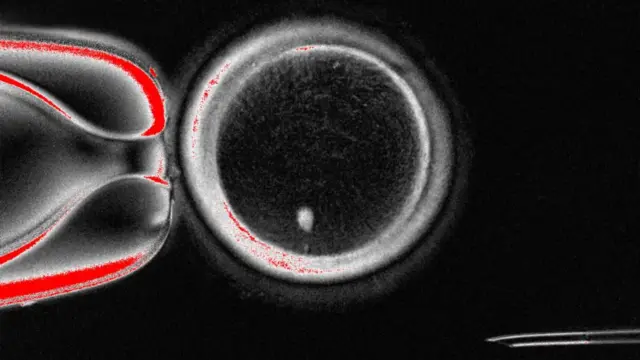

Iwadii ti 'The Oregon Health and Science University'', ṣe ni wọn fi gbe kinni kan kalẹ ti wọn gbe ọlẹ naa si- eyi ti wọn fi awọ ara pilẹ rẹ.

Lẹyin eyi ni wọn yoo gbe e sinu ẹyin obinrin ti wọn ti gba, lai fi ti ẹni to ni ẹyin naa ṣe.

Nibi ti wọn ba a de bayii, ilana yii fẹẹ da bii iru eyi ti wọn fi ṣe 'Dolly the Sheep' – iyẹn ẹranko akọkọ ti wọn ṣe ni 1996 lai si pe ẹranko meji ba ara wọn laṣepọ.

Ṣugbọn ṣaa, ẹyin ti a n wo yii ko ti i ṣetan ti yoo di ọmọ nipasẹ atọ, nitori o ti ni awọn nnkan ayipada ti a mọ si chromosomes ninu.

Mẹtalelogun ( 23) iru awọn nnkan yii ni ọmọ maa n mu lara iya ati baba rẹ ninu DNA wọn nikọọkan. Apapọ rẹ yoo si jẹ marundinlaadọta (46), eyi to ti wa lara ẹyin atọwọda yii ni tiẹ.

Fun idi eyi, ipele to kan ni lati rọ ẹyin naa pe ko ja idaji ninu awọn chromosomes yii kuro, eyi ni awọn oniwadii n pe ni "mitomeiosis" (itumọ ọrọ naa ni idapọ mitosis ati meiosis, iyẹn ọna meji ti sẹẹli ara pin si).

Iwadii ti wọn gbe jade ninu Journal Nature Communications, fi han pe ẹyin 82 to ṣiṣẹ daadaa ni wọn pese. Atọ ni won fi pese wọn, awọn kan si di ọlẹ, ṣugbọn ko si eyi to kọja ọjọ mẹfa ninu wọn.